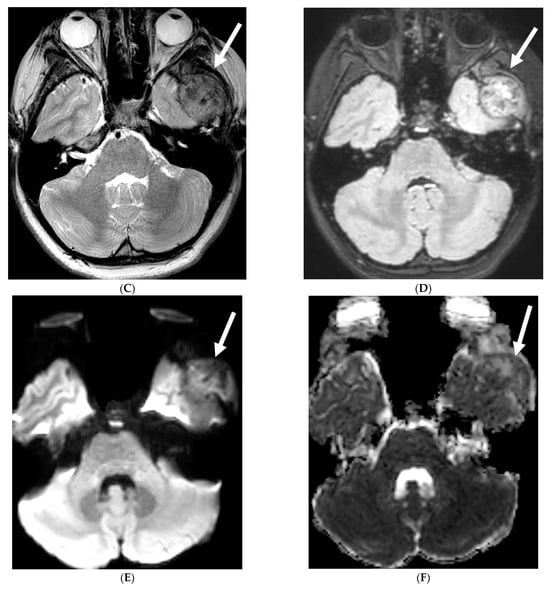

3.6. Glioneuronal Tumor

Diffuse leptomeningeal glioneuronal tumor (DL-GNT) is a recently classified brain tumor (WHO 2016) previously known by various terms such as disseminated oligodendroglial-like leptomeningeal tumor, dysembryoplastic neuroepithelial tumor-like neoplasm and meningeal gliomatosis [52]. It is also associated with precancerous conditions such as KIAA1549-BRAF gene fusion, 1p deletion or 1p/19q co-deletion and Haberland syndrome [53,54].

Although a low-grade neoplasm, leptomeningeal spread is the norm [55]. DL-GNT is characterized by diffuse leptomeningeal thickening, often with basal predominant nodular enhancement [56]. There is invariable involvement of the leptomeninges along the spinal cord in linear fashion [57]. Distinctively, numerous small T2-hyperintense parenchymal cysts are present as a result of fibrosis and obstruction in the subarachnoid space; typically in the inferior frontal and medial temporal lobes [53]. These cysts show incomplete signal suppression on T1 and FLAIR images, possibly reflecting their mucoid nature [53,57]. Engulfment of peripheral nerve roots and invasion of choroid plexus may be seen (Figure 6) [55]. The diagnosis of DL-GNT be pursued with characteristic imaging findings with infectious etiology been ruled out [56].

Figure 6.

Axial FLAIR (A), Axial T2 orbits (B), Axial T1 orbits post contrast (C) and axial T1 post contrast (D): 13-year-old female with headache and blurred vision. Abnormal FLAIR hyperintensity involving the left parieto-occipital periventricular white matter (arrow), and bilateral cerebellar hemispheres. Bilateral papilledema (black arrow) and edematous left optic nerve (dashed arrow). Peripheral optic nerves/optic sheath enhancement in the posterior aspect (curved arrows). Demyelination, infectious and metastatic processes were considered. MRI brain 6 months later with persistent symptoms demonstrates patchy and asymmetric pachymeningeal and leptomeningeal enhancement (open arrows). Pathology: Diffuse Leptomeningeal Glioneuronal Tumor.

3.7. Primary Leptomeningeal Rhabdomyosarcoma

Rhabdomyosarcoma, the most common childhood soft tissue sarcoma, is commonly seen in the head and neck, genitourinary tract and extremity [58]. Primary meningeal rhabdomyosarcoma is extremely rare [59,60]. It is hypothesized that the origin of this rare variant is cerebral parenchyma with secondary leptomeningeal spread [61].

Diffuse LME with areas of leptomeningeal thickening and nodularity would be the prominent imaging finding which may cause hydrocephalus. These findings mimic more common entities such as infection (e.g., tuberculosis) or inflammation (e.g., neurosarcoidosis).

Marked focal nodularity and mass effect causing a deformed contour on the spinal cord favor a neoplastic process (Figure 7) [62]. Accurate staging is crucial as the presence of leptomeningeal or multifocal disease have implications on radiotherapy fields and total dose. Additionally, PET-CT scan assists in evaluating for an extracranial primary site [63].

Figure 7.

3-year-old boy with 2 weeks history of headache and vomiting. Axial FLAIR (A), post contrast axial T1 FS (B) and sagittal 3D inversion recovery (C) images demonstrate FLAIR hyperintensity in the interpedencular cistern (curved arrow) and mild hydrocephalus. Extensive meningeal enhancement most prominent at the skull base, basal cisterns, and Sylvain fissures (arrows), but extending throughout the brain. There is meningeal enhancement, with coating of the brainstem extends inferiorly along the cervical spinal cord (dashed arrows). Sagittal T2 (D), sagittal T1 (E) and fat saturated T1 post (F) images show extensive leptomeningeal with predominantly solid and some cystic nodules (curved arrows) on T2 sequence and isointense on T1 (arrows). Lesions predominantly involve the posterior spinal canal, causing mass effect and anterior displacement of the spinal cord. The solid nodules show enhancement after contrast injection and extensive uniform diffuse LME around the cord (dashed arrows). Pathology: Primary Meningeal Rhabdomyosarcoma.